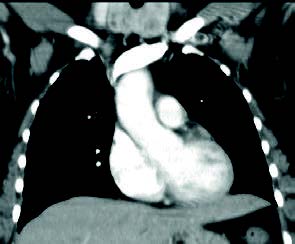

Mujer de 46 años que consulta por disfonía desde hace 2 meses, no fumadora, con antecedentes de hipertensión arterial y colesterol alto. En la exploración con fibroscopia naso-laríngea se aprecia parálisis de cuerda vocal izquierda. Como protocolo de las parálisis recurrenciales se pide TAC cérvico-torácico, para valorar el trayecto del nervio recurrente laríngeo, donde no se observan lesiones en mediastino o pulmón. Se aprecia gran crecimiento de la glándula tiroidea con lesiones quísticas y nodulares más intensas en lóbulo tiroideo izquierdo: bocio multinodular.